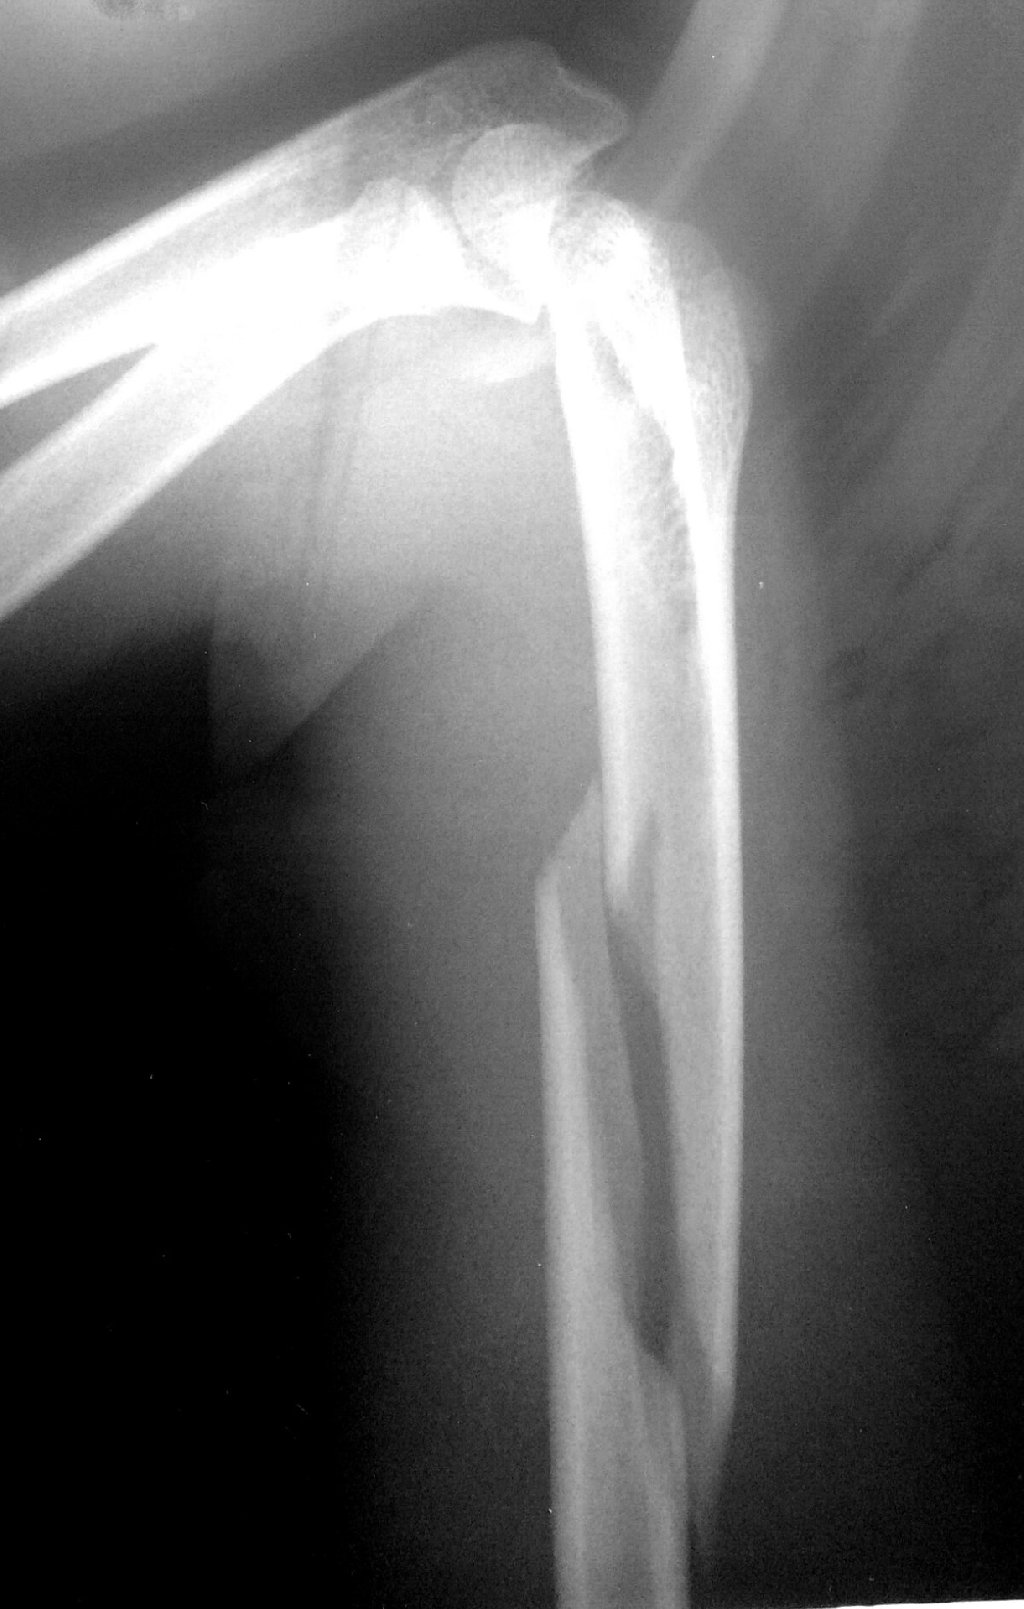

Sınıq Növləri Çiyin sümüyünün sınıqları müxtəlif növlərə bölünə bilər, bunlar arasında: Korako ...

Çiyin Zədələnmələri Çiyin Dislokasiyası (Çıxıq) Təsviri: Çiyin oynağı sümüklərin bir-birindən ...

Sınıqlar: Uşaqlarda ən çox rast gəlinən travma növü sınıqlardır. Ən çox qol və ayaq sümüklərində ...